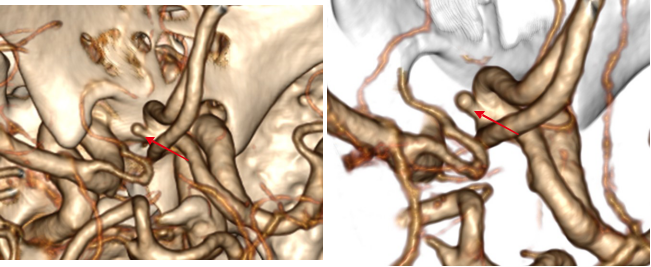

病例四 男,64歲, 頭暈胸悶查因。 執(zhí)行頭頸血管+心臟冠脈一站式低劑量掃描。

一次掃描 、一次打藥60ml完成頭頸心一站式掃描,各血管及小分支清晰可見(jiàn) , 頸 部 血管未見(jiàn)明顯異常, 冠脈有狹窄及多發(fā)斑塊。

病例一 女, 78 歲,心前區(qū)輕度疼痛, 胸悶氣短, 行冠脈CTA檢查HR 57 - 120 bpm。

病例二 男,30歲, 右心房占位性病變,心功能Ⅱ級(jí),心律失常,心房纖顫, 平均心室率92次/分。

術(shù)前CT檢查:

右心房增大,其內(nèi)可見(jiàn)占位性病變,通過(guò)獨(dú)有的三維染色后處理,可以對(duì)腫瘤進(jìn)行染色, 以便于確定腫塊與心臟血管及其他周圍結(jié)構(gòu)的關(guān)系。

心臟彩超及食道超聲可見(jiàn)右房?jī)?nèi)囊性占位病變;室間隔及左室壁厚度正常高限;雙房大; 左室收縮功能正常; 彩色血流示: 各瓣膜未見(jiàn)病理性返流。

腫瘤病理結(jié)果與CT檢查顯示的大小、 形態(tài)相符合。

術(shù)后CT檢查:

術(shù)后可見(jiàn)右房形態(tài)正常, 心臟其余各結(jié)構(gòu)未見(jiàn)明顯異常。

640層寬體探測(cè)器CT實(shí)現(xiàn)了3 20排譜黃金寬體探測(cè)器1 6 cm的 超寬覆蓋范圍, 與2 7 ms超 快時(shí) 間 分 辨 率 的 完 美 結(jié) 合 , 可 以 實(shí) 現(xiàn) 微 劑 量 高 清 全 景 電 影 成 像 。 特 別 是 在 冠 脈 檢 查 上 , 可 以 實(shí) 現(xiàn)一次心跳下的心臟冠脈檢查, 實(shí)現(xiàn)復(fù)雜心率情況下高清冠脈成像的100 % 檢查成功率。

此外,強(qiáng)大的后處理功能,能提取心臟冠脈,明確腫瘤大小、形態(tài)、表面特征、位置及三維展示與周圍結(jié)構(gòu)的關(guān)系,還能提供心功能等各項(xiàng)參數(shù),以便臨床對(duì)心臟情況做一個(gè)充分的評(píng)估,術(shù)前充分設(shè)計(jì)好方案尤為重要。